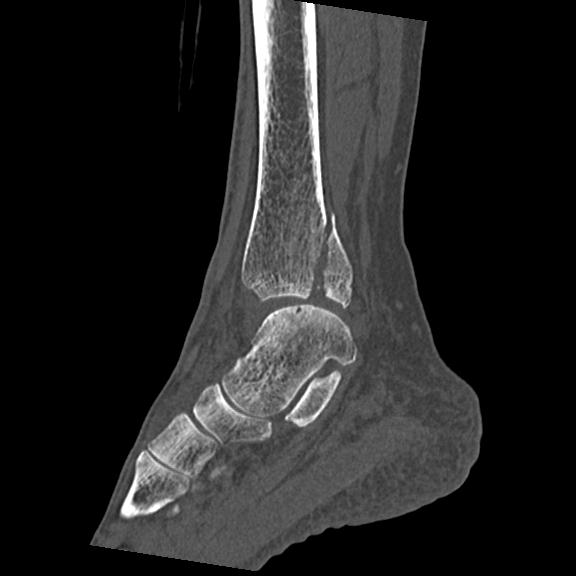

56476 8/28 4R 1/21 2R 左足関節 デジカメ写真 72歳女性 右足関節AS

102755 1/4 2R 1/15 2R 右足関節 68歳女性 右三果脱臼骨折